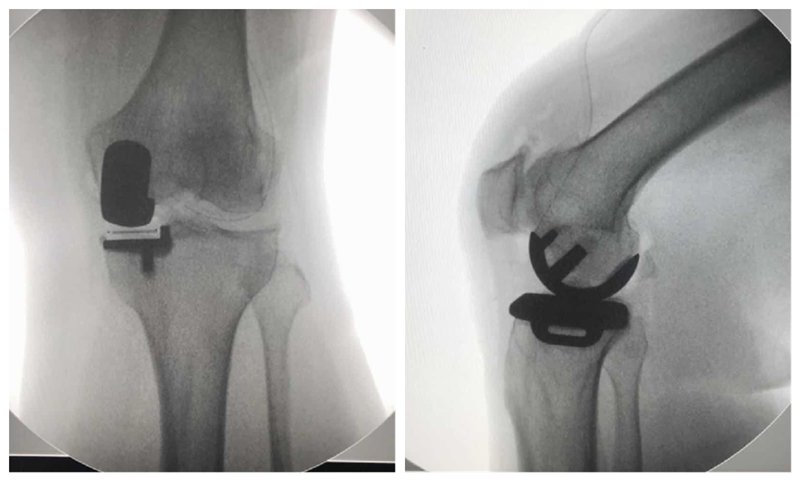

高龄患者内侧单髁置换术

术前

术后检查

对于80岁以上的高龄膝关节骨关节炎患者,准确手术评估、恰当围术期处理、选择微创UKA,不仅有效,而且安全可行。与TKA相比,高龄患者采用UKA治疗不仅有效,还具有并发症少、输血率低、住院时间短、恢复快等特点。但是,高龄膝关节骨关节炎患者通常合并较多内科疾病,围术期科学管理尤为重要。应注意以下几点:术前高血压患者血压应控制在160/90 mm Hg以内;糖尿病患者血糖应控制在10.0 mmol/L以内,尿糖(+++);冠状动脉粥样性硬化病患者适当给予扩张冠脉及营养心肌治疗,超声心动图示左心室射血分数超过 50%以上;心律失常患者完善24 h动态心律检测,必要时请心内科协助诊治;慢性肺部疾病患者肺功能最大通气量超过 60%以上。另外,术前需关注贫血及低蛋白血症情况,必要时给予输血或补充白蛋白治疗。熟练操作、严格微创、减少手术时间及术中出血是手术成功关键。

严重内翻畸形单髁置换术

严重内翻畸形需要明确畸形原因,对于骨缺损明显,膝关节僵直畸形,合并内侧副韧带挛缩,畸形>20°病例不适合。对于在外翻应力位可以矫正的关节内的内翻畸形,只要前交叉韧带完整,仍然可以谨慎选择UKA。术前仔细评估骨质磨损深度,骨缺损,内侧副韧带张力及膝关节稳定性。备好全膝关节假体。术中注意避免截骨过深,导致间隙过大,常规厚度假体不能满足需要。骨质缺损较多一般推荐使用固定垫片假体。注意保护内侧副韧带,避免截骨损伤。